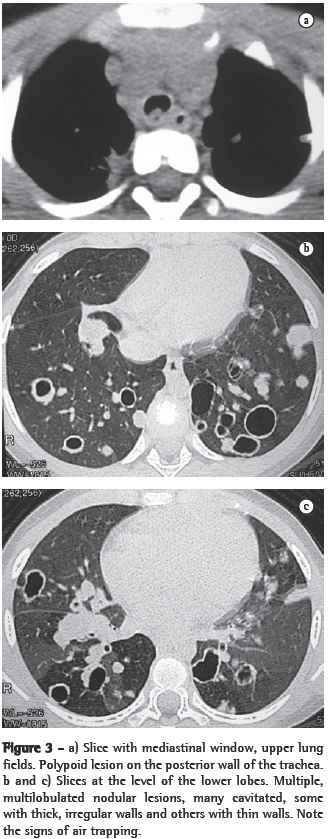

In all eight cases, the CT scans revealed polypoid formations in the trachea. In one case, injury to one of the main bronchi was identified. Seven patients presented involvement of the pulmonary parenchyma. In all eight cases, there were cavitated polypoid lesions, with irregular internal borders and walls of various thicknesses, multilobulated in six cases and presenting confluence of the lesions in five (Figures 1 through 5). Solid nodules were seen in six patients. An air-fluid level was observed in only one patient. The lesions were predominantly in the lung bases in three patients and in the middle thirds in two, whereas they were evenly distributed in two. In one patient, the lesions were accompanied by a mass, and, in another patient, they were accompanied by consolidation. In the latter case (Figure 5), there was malignant degeneration in multiple lesions. Signs of air trapping were also observed in one case. There were no identified instances of lymph node enlargement or pleural effusion.

Chest X-rays can occasionally produce findings suggestive of the disease, such as the combination of solid or cavitated pulmonary nodules and vegetative nodular lesions in the trachea or in the main bronchi. Unlike the pulmonary nodules, which are often identified on simple chest X-rays, intralumen papillomas in the trachea or bronchi are rarely visible on X-rays.(4) In practice, therefore, the disease is rarely diagnosed on the basis of chest X-ray findings. The nodules are typically multiple, well defined, of various dimensions, cavitated and thick-walled, being more numerous in the basal and posterior lung regions.(3,4) The cavitated nodules can be air-filled or, when infected, can present an air-fluid level.(4)

Chest X-rays are inferior to CT scans of the chest, especially those performed using spiral CT (volumetric acquisition), in the initial phases of pulmonary dissemination, due to the fact that CT better characterizes and allows better visualization of nodular tracheobronchial vegetation, Tomographic findings include focal or diffuse airway narrowing caused by the nodules. The nodules form on the mucosal surface, and their invasion into the lumen is best evaluated using CT.(3) These alterations are easily correlated with the disease when there is a clinical history of papillomatosis.(4) Other findings related to airway obstruction and accompanying infections are atelectasis, consolidations, air trapping and bronchiectasis.(2-4) In our sample, polypoid formations in the trachea were observed on all of the CT scans Seven patients presented involvement of the pulmonary parenchyma, characterized by cavitated polypoid lesions with irregular internal borders and walls of various thicknesses, with a multilobulated aspect and a tendency toward confluence. Solid nodules were seen in six patients. None of the patients presented lymph node enlargement or pleural effusion.